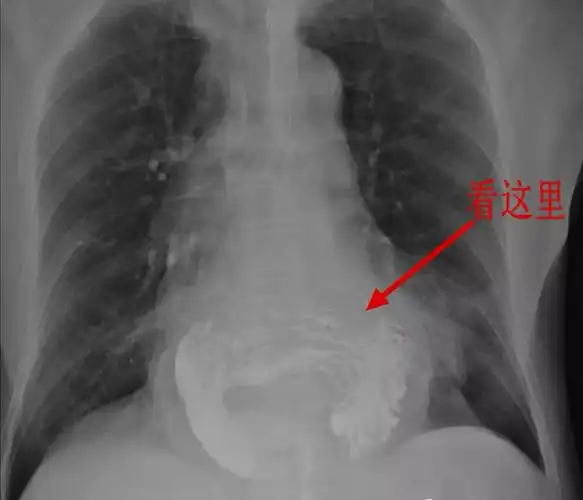

经典影像之食管裂孔疝 - 好大夫在线